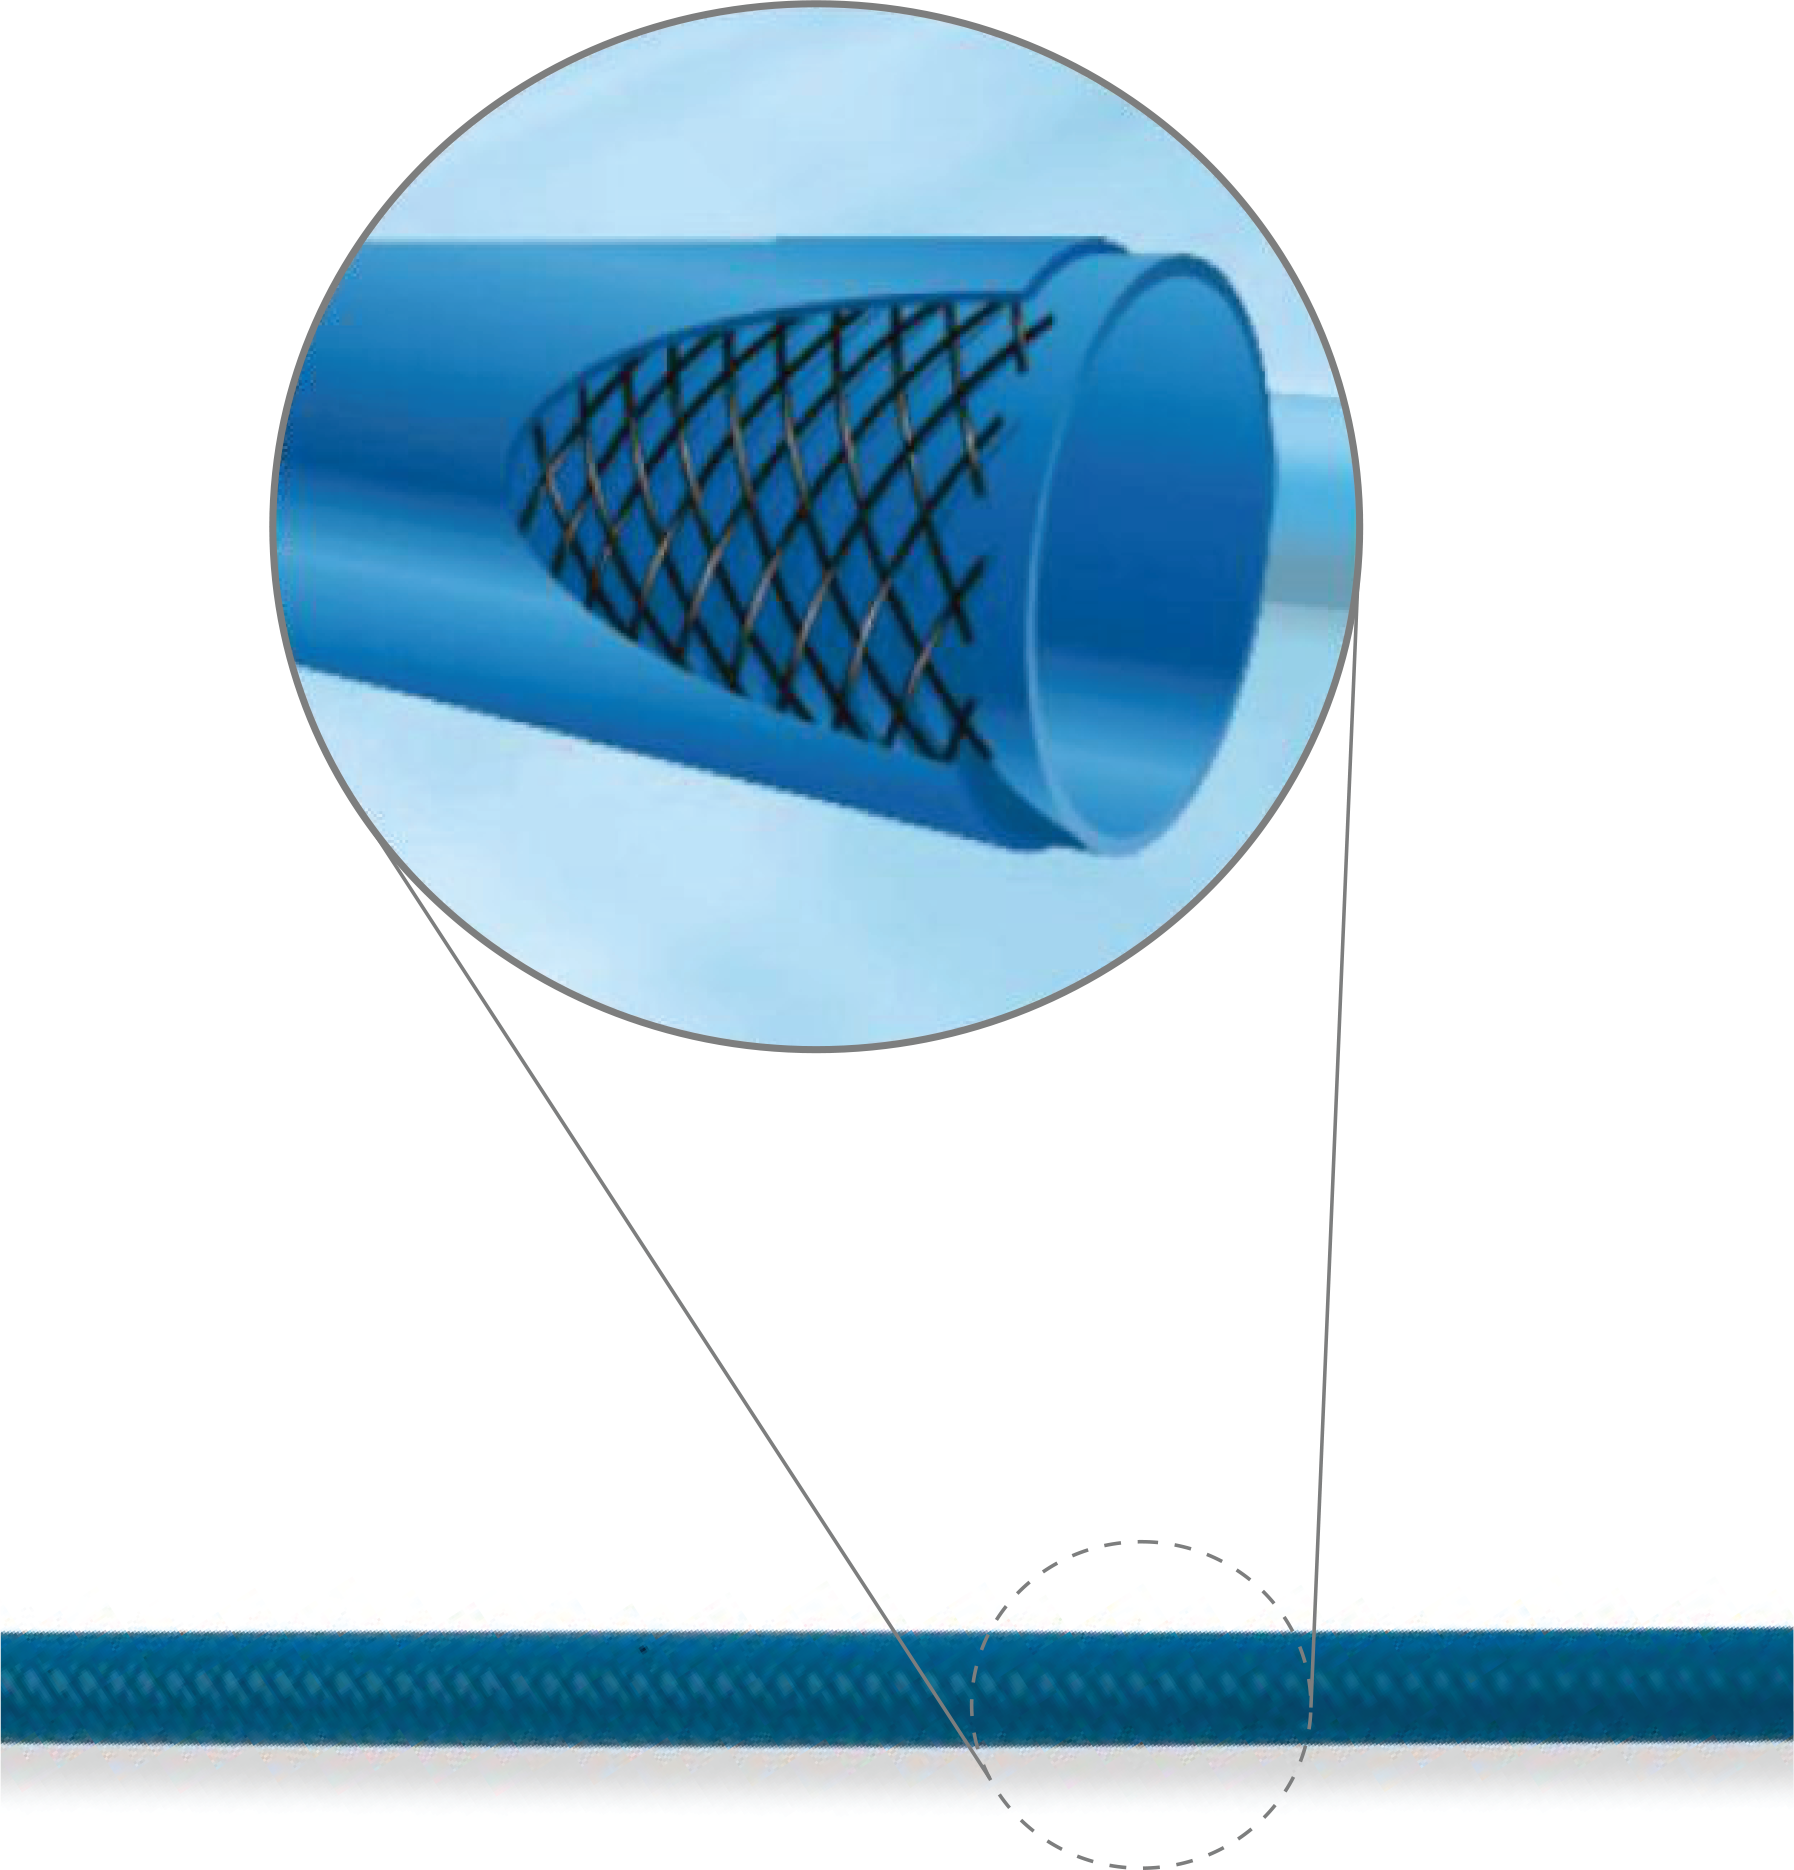

Diagnostic Catheter

Features & Benefits

-

Unique hydrodynamic surface

• Results in low resistance

• Less Vessel Spasm

• Superior Surface Smoothness -

Atraumatic soft tip

• Prevents dissections & pertorations -

Superior kink resistance

• Double wire stainless steel braiding

• High flexibility -

Material

• Polyamide -

Large inner lumen

• Guarantees easy & complete contrast filling for optimal vessel opacitication -

Excellent Torque control

• 1:1 Torque

• Hub with grip section for optimal torque control